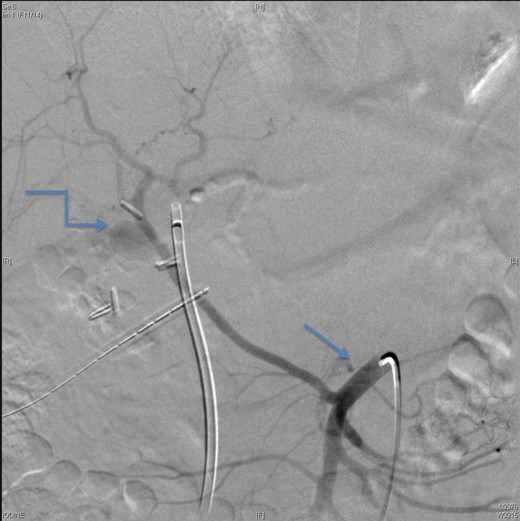

Upon presentation to our center, the patient was febrile (38.9°C) and complained of a left upper limb pain and swelling. The surgical drain was draining a mixture of bile and blood. His WBC count was 14 × 109/l, total bilirubin 35 µmol/l and the direct bilirubin 21 µmol/l. A duplex ultrasound of the upper limb revealed a left brachial vein thrombosis. Hematology was consulted, and a diagnosis of acute upper limb venous thrombosis was established. Owing to the presence of blood in the drain, he was kept on the maximum prophylactic dose of unfractionated heparin. A CT angiography of the abdomen showed two collections, one at the surgical bed near the drain, and the other was subcapsular below the left lateral lobe of the liver, as well as an aneurysm of the replaced right hepatic artery with an active bleeding blush (Fig. 1). The patient was immediately referred for an angiography, which confirmed the CT scan findings (Fig. 2). An arterial stent was inserted at the location of the aneurysm (Fig. 3), and a pigtail drain was inserted to drain any residual collection. An ERCP was also performed, which revealed a Strasberg Class D injury, and a plastic biliary stent was inserted. After the angio-stent insertion and stabilization of the patient, heparin infusion was started. Five days later he developed hematemesis and melena with a significant drop in his Hb to 2 g/l, and his total bilirubin became 183 μmol/l of which 91 μmol/l is direct. A gastroscopy was performed and showed hemobilia (bleeding from the ampulla of Vater). Subsequent angiography demonstrated a leak of contrast just above the arterial stent; hence, a further stent was placed to cover that area of the aneurysm. Similar symptoms reoccurred a week later, and a new angiography showed a new aneurysm from the left proper hepatic artery. A percutaneous thrombin injection of the aneurysm was performed as the bleeding branch was unreached via direct angiography and was filling in retrograde perfusion. During recovery a chest spiral CT was performed, which revealed the diagnosis of a bilateral segmental pulmonary embolism. Heparin infusion with low targets of partial thromboplastin time of 50–60 was started.

An angiographic scan showed superior mesenteric artery (straight arrow) and replaced right HAP (angulated arrow).